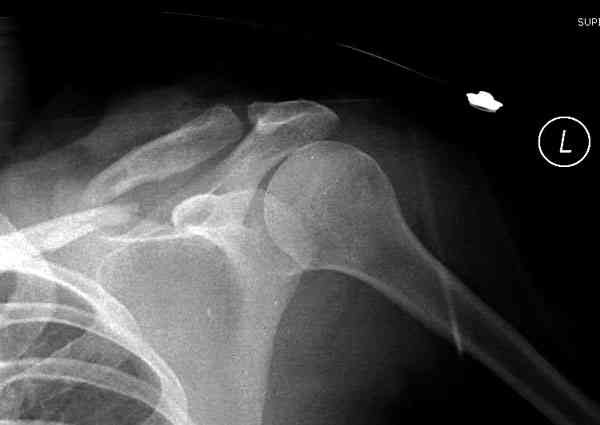

Недавно разбирали случай ложного сустава.

45 летная женщина после автоаварии, алкоголь 163 и 20 летним стажем курения.

Консервативное лечение, через 8 мес. операция Rockwood pin с костной пластикой в нашем городе другим врачом. После 8 недели падение, гвоздь удален оперирующим хирургом, больная направлена к нам. Фиксация реконструктивной пластиной с трикортикальным графтом, добавлен BMP-2. Для стабилизации фиксацию провели через акромион.

Вот уже два месяца больная также продолжает жаловаться на боли, буквально на днях удалили акромиальную часть пластины с специальной пилой с алмазным покрытием для медицинского металла. До сих пор судьба ложного сустава неизвестна....